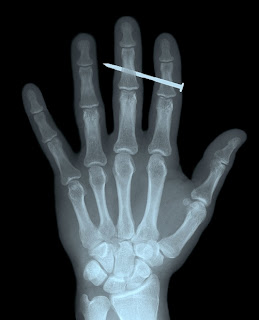

Gambar: X-ray paling pelik dunia!

Macam mana? Ada berani tak? Kena tusuk paku beb! Lain kali kalau dapat x-ray macam ni, jangan terkejut er!